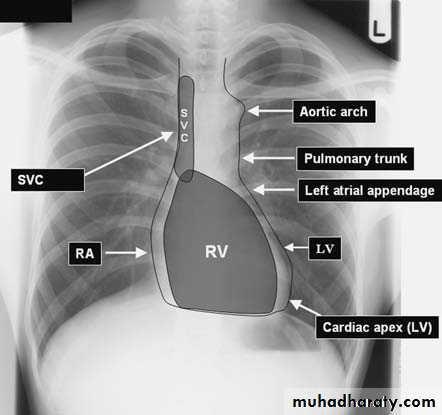

Mediastinum

1)Trachea & main bronchi 2) esophagus3)Heart &major vessels

4)LNs

5)Nerves

6) Thymus